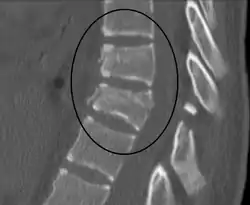

![]() كسر تشانس عند T10 وكسر T9 بسبب حِزام المَقعد خلال تَصَادُم سيَّارة. كسر تشانس عند T10 وكسر T9 بسبب حِزام المَقعد خلال تَصَادُم سيَّارة. | |

يُنصَح بالتَفَرُّس المَقْطَعِيّ المُحَوسَب للصدر والبطن والحوض كجزء من العمل التشخيصيّ للتحقُّق من وجود إصابات بَطنيَّة مُحتملة،[6][10] وقد يكون التَّصوير بالرَّنين المغناطيسيّ مُفيدًا أيضًا.[10] غالبًا ما يكون الكسر غير ثابتٍ.[1]